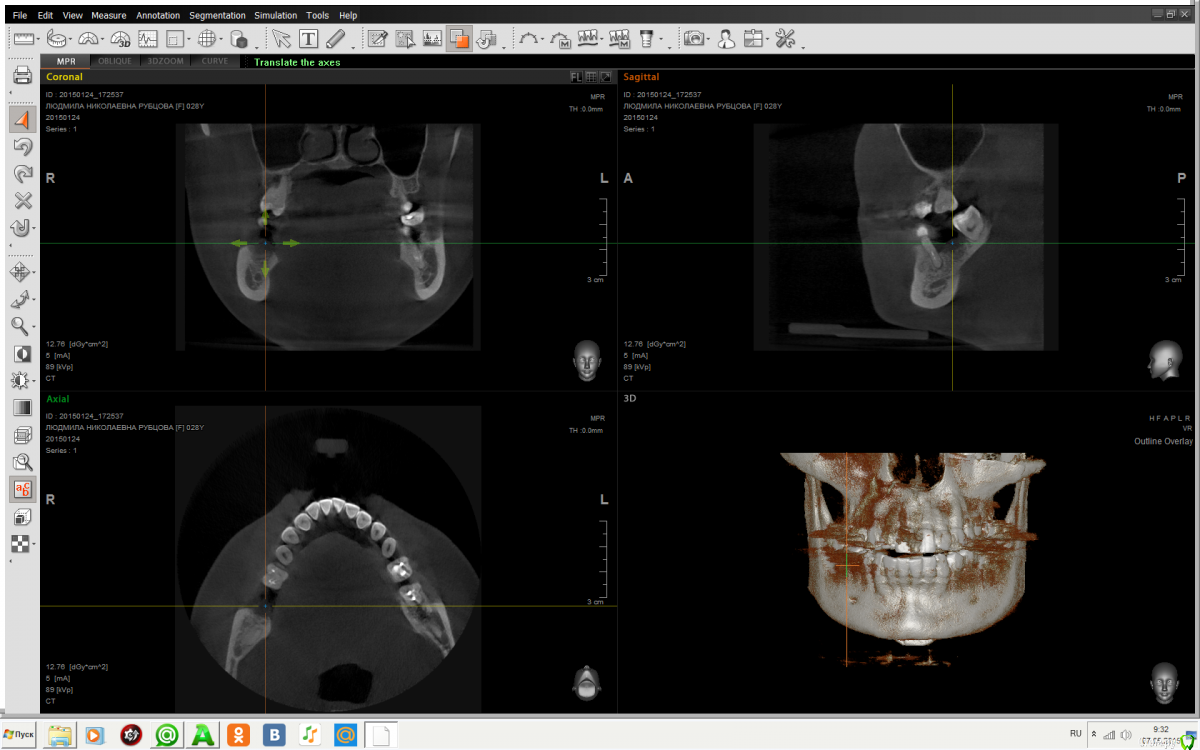

mila28 Опубликовано 7 мая, 2015 Поделиться Опубликовано 7 мая, 2015 Добрый день. Посоветуйте пожалуйста можно ли обойтись без костной пластики? Сделала скрин КТ, но не знаю правильно или нет, я в этом ничего не понимаю Ссылка на комментарий

Bier Опубликовано 7 мая, 2015 Поделиться Опубликовано 7 мая, 2015 если речь идет о 7м нижнем справа, то не нужна Ссылка на комментарий

mila28 Опубликовано 7 мая, 2015 Автор Поделиться Опубликовано 7 мая, 2015 Спасибо. Именно о нем речь. Врач насчитал костной пластики аж на 50000 Ссылка на комментарий

Mane Опубликовано 8 мая, 2015 Поделиться Опубликовано 8 мая, 2015 Мила, действительно, установить 7-нижний можно и без костной пластики. Но это только по этому срезу. У вас там проблема с соседом. Пахнет удалением. Я бы рассматривал имплантацию сразу двух Ссылка на комментарий